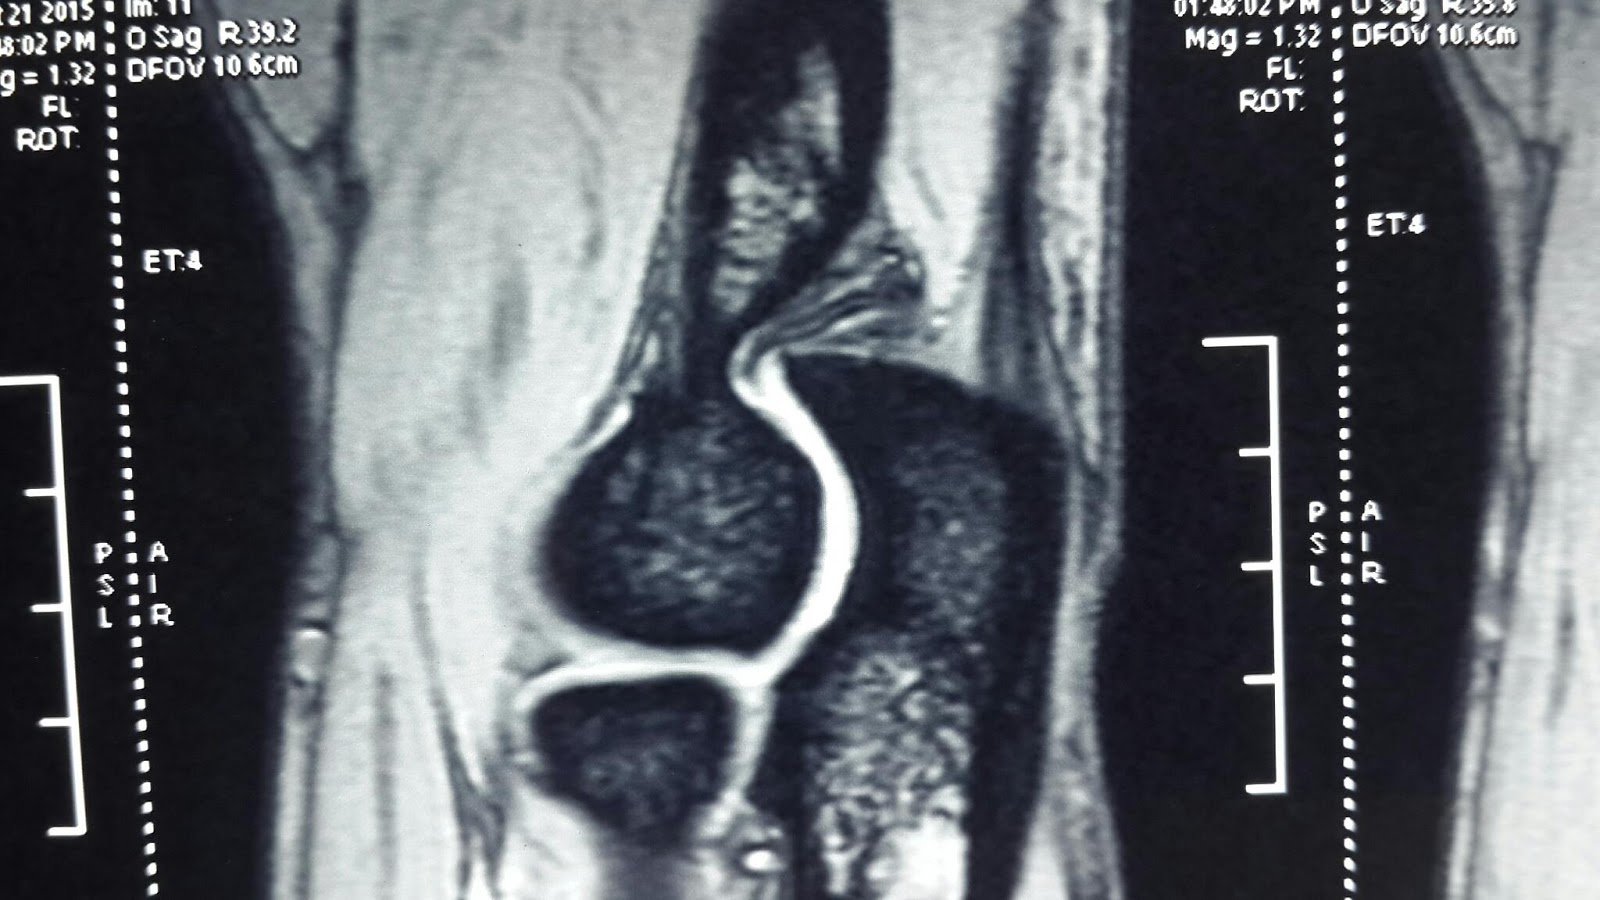

Has your orthopedic surgeon offered you knee arthroscopy for a meniscal tear? Don't waste your money on it. Even if it is not your money and insurance is paying for it, still you should not waste your time and effort on it. A recent editorial from a leading Orthopedic journal opines that routine knee arthroscopy is a waste of time. This finding only re echoes a leading paper published in 2002 in the New England journal of medicine. Read the news here.